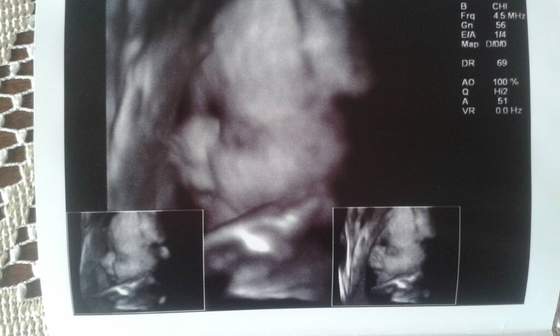

Oto mój mały wielki Skarb :-)

Pat gratuluję tej 5! Pewnie będzie ich więcej. Trzymam mocno kciuki :-) mój szkrab też się strasznie kręci. Raz kopie po pęcherzu, za chwilę bombie po zebrach![]()